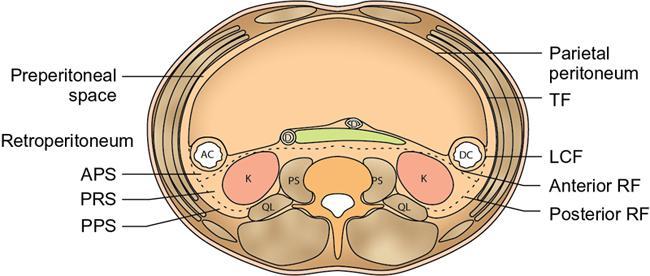

CROSS SECTIONAL ANATOMY OF ABDOMEN Satya Jha NORMAL ANATOMY OF ABDOMEN AND PELVIS Amandeep Singh The two major surfaces: The anterior and posterior layers of the coronary ligament converge on bare area (not covered by peritoneum). Its right and left margins form the right and left triangular ligaments. The right triangular ligament extends toward the diaphragm and separates right subphrenic space from right subhepatic space. The left triangular ligament gives tracts extending to the diaphragm and falciform ligament and does not compartmentalize the left subphrenic space. Ligamentum teres or the obliterated umblical vein is contained in falciform ligament which attaches the liver to anterior abdominal wall. The main portal vein, the proper hepatic artery and the common bile duct are contained within investing peritoneal folds of hepatoduodenal ligament at the porta hepatis (Fig. 7.2.2.1). Liver is divided into eight segments which are functionally independent and have their own vascular supply and biliary drainage. Arterial circulation: The branches of the hepatic artery accompanying the portal veins. Hepatic venous system: The right, middle, and left hepatic veins draining into IVC (Figs. 7.2.2.2 and 7.2.2.3). The gallbladder is a blind pear-shaped muscular membranous sac which is an embryologic derivative of the foregut, is a pouch lying along the undersurface of the liver. The gallbladder fossa is located in the plane of the interlobar fissure, which lies between the right and left hepatic lobes. Its major function is to store and concentrate bile which is produced by the liver. It measures approximately 4 cm in diameter when it is normally distended. Gallbladder is a smaller tubular structure in contracted state. The normal gallbladder wall thickness ranges from 1 to 3 mm. The gallbladder is divided into the fundus, body and neck. Infundibulum is present in the region of neck of the gallbladder, which is called the Hartmann pouch, where gallstones are usually impacted. Intrahepatic biliary radicles (IHBRs) scattered throughout the liver get confluent towards the hilum. They unite to form the right and left main hepatic ducts which further unite to form common hepatic duct (CHD) at the hilum. Common bile duct is formed by the union of cystic duct with common hepatic duct. The main pancreatic duct is joined with the common bile duct to form the ampulla of Vater at the major duodenal papilla (Figs. 7.2.2.4 and 7.2.2.5). Pancreas is located in anterior pararenal space of retroperitoneum anterior to perirenal (Gerota’s) fascia and posterior to parietal peritoneum. It is divided into head, uncinate process, neck, body and tail from right to left. Pancreas lies anterior to portal vein, which marks the point of transition between the body and neck. The region between head of pancreas and second and third parts of duodenum is known as the pancreatic groove. In postnephrectomy cases or with agenesis of kidney or ectopic kidney, pancreas moves posteriorly to partially fill in the empty renal fossa; its soft tissue density should not be mistaken for recurrent tumour. It is located in the pancreatic groove and is bounded superiorly by the duodenal bulb, laterally by second portion of duodenum, inferiorly by third portion of duodenum, medially by superior mesenteric vein and anterior to inferior vena cava. It is a wedge or wedge shaped lying posterior to superior mesenteric artery and vein. It is an imaginary junction between the head and body and lies directly over the junction of the splenic vein and superior mesenteric vein. It is located posterior to the lesser sac and anterior to the aorta, left adrenal gland, left kidney, and renal vessels and runs obliquely upward to the left of the superior mesenteric vessels. It is situated median to the colonic flexure and anterior to the left kidney. It is located in close proximity to the splenic hilum without a notable relation with the body of pancreas. It is seen anterior to the left kidney and median to the colonic flexure. The distal part of the tail passes between the peritoneal layers of the splenorenal ligament (Fig. 7.2.2.6 and 7.2.2.7).

Pancreas

Normal anatomy and relationships of pancreas